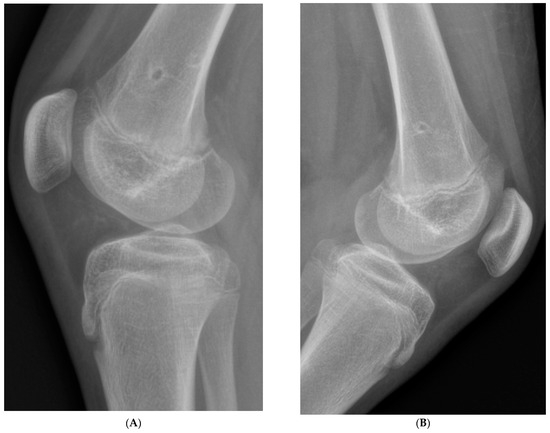

All procedures were performed by staff surgeons with specialized expertise in pediatric orthopedic surgery. Patients were positioned supine on a radiolucent table. Under general anesthesia and with the application of a tourniquet, the 8-plates were inserted with C-arm fluoroscopic guidance. The plates were applied laterally and medially, with screws placed above and below the distal femoral growth plate, angled obliquely to the long axis of the bone in opposing directions (Figure 1). Efforts were made to achieve the largest possible angle between the lateral and medial 8-plates without compromising the growth plate. For external rotation correction, the 8-plate was positioned medially, with the screws placed obliquely from a superior-anterior to an inferior-posterior direction, and laterally from a superior-posterior to an inferior-anterior direction. For internal rotation correction, the plates were positioned in the opposite directions. A skin incision of approximately 2 cm was required. The operative technique for 8-plate application remained unchanged.

Figure 1. Intraoperative radiographs of an 8-plate positioned obliquely for RGG, with (A) showing the lateral view and (B) showing the anteroposterior (AP) view.